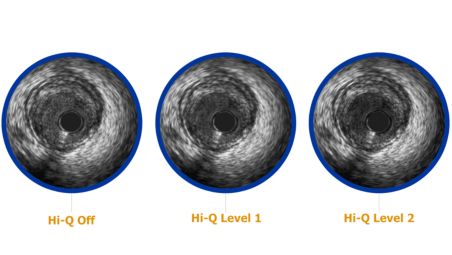

3 Hi-Q imaging options

Choose from three high-quality, optimized imaging modes with varying levels of darkness and fineness of blood speckle to assist in differentiating between tissue and blood along the lumen border. High-quality image enhancement is available on all Revolution catheters using Philips IVUS systems with version 3.3 software and higher. Hi-Q imaging modes are accessible via the “Adjust Image” menu.